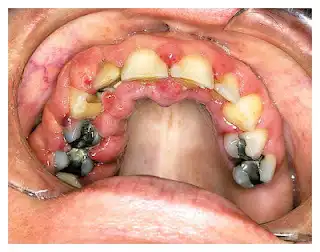

Бегом к стоматологу

Хронический фиброматозный гингивит. Бывает и страшнее